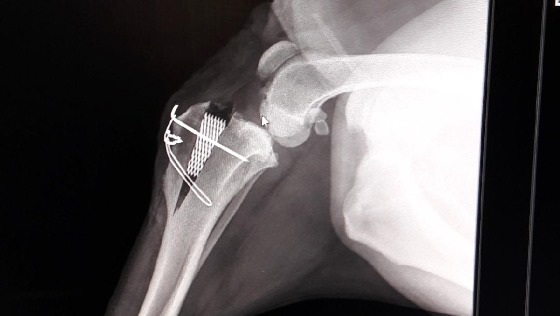

Cześć !! Nazywam się Bongo i mam 3 lata. Jako pies mogę powiedzieć, że nie miałem łatwo... urodziłem się w psełdo-hodowli labladorów w fatalnych warunkach, mało nie utonąłem w błocie i brudzie jaki tam panował, dzięki reakcji odpowiednich służb trafiłem do fundacji skąd moja Pańcia zabrała mnie do ciepłego, pełnego rodziny domu z wielkim podwórkiem gdzie biegałem całymi dniami a wieczorami oglądałem TV z moją Panią. Niestety sielanka nie trwała długo, szybko zdiagnozowali u mnie dysplazje ale nie poddawałem się, od razu wdrożono mi odpowiednie leki i byłem całkiem w dobrej formie, aż do kolejnego nieszczęścia. Podczas jednego ze spacerów zerwałem w tylnej łapie więzadło krzyżowe. Moja ukochana Pani nie zastanawiała się ani chwili, po szeregu konsultacji trafiłem do wybitnych fachowców z Puławskiego Centrum Weterynaryjnego, gdzie wszczepiono mi implant. Niestety koszty leczenia są bardzo wysokie, boję się, że budżet mojej opiekunki może tego nie wytrzymać!!!